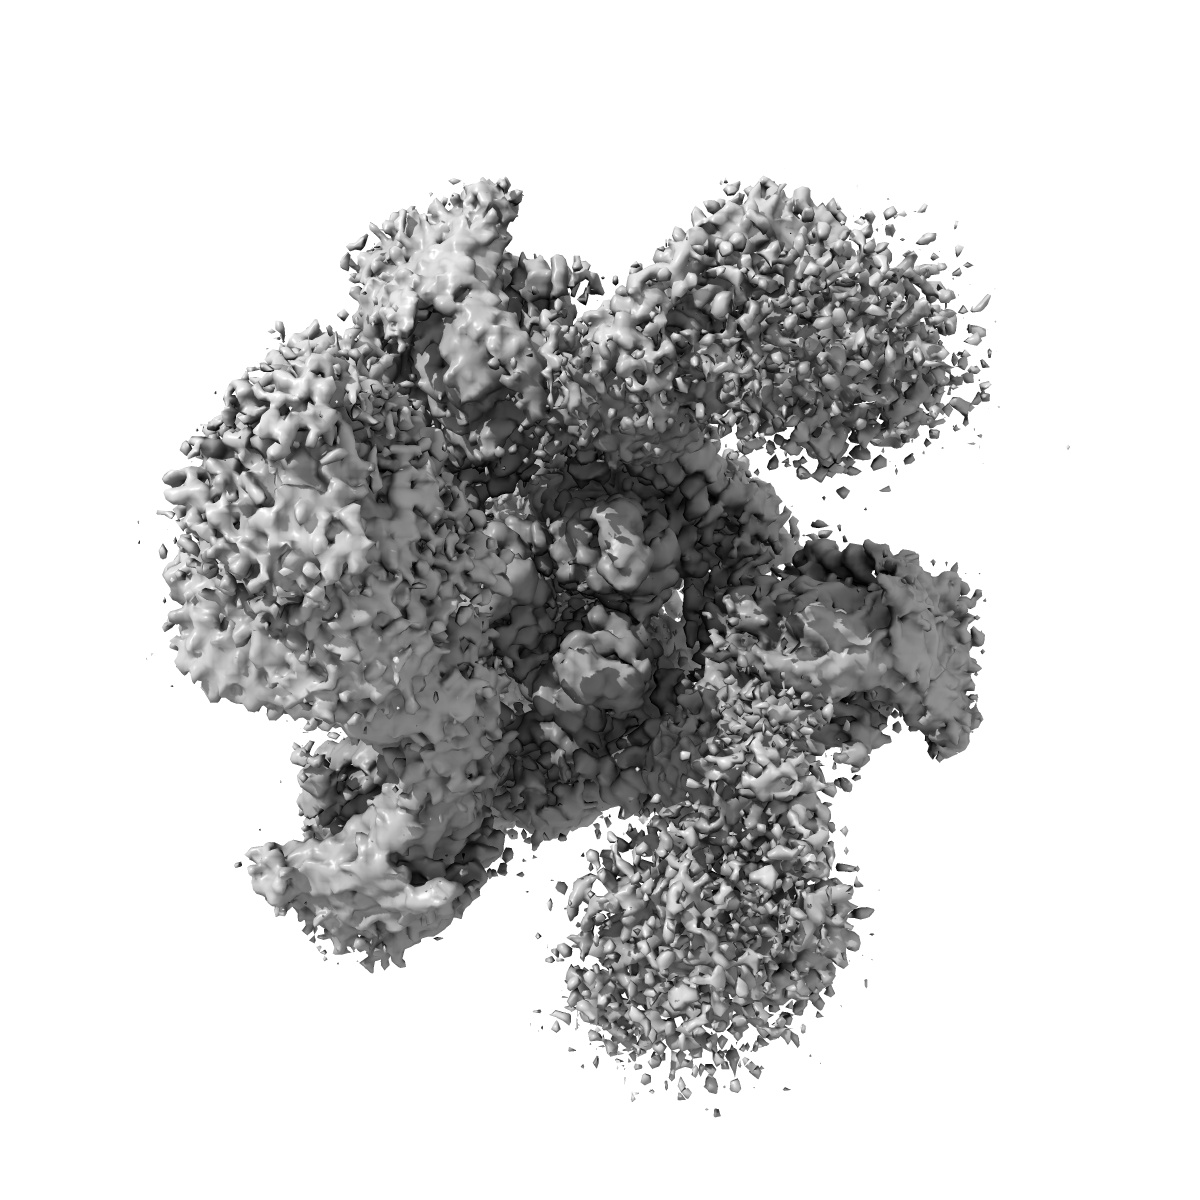

Cryo-EM structure of SARS-CoV-2 S-Kappa variant (B.1.617.1) in complex with Angiotensin-converting enzyme 2 (ACE2) ectodomain, three ACE2-bound form